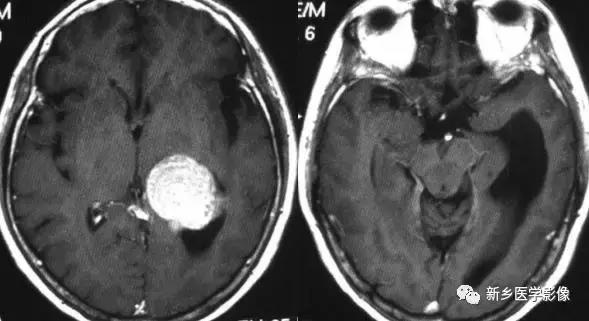

1.导水管狭窄:

中脑导水管是脑室系统最狭窄的通道,也是脑脊液循环受阻最常见的部位。

导水管狭窄的病因比较复杂、主要包括:①先天发育性狭窄②导水管周围胶样变③导水管粘连等。先天发育性狭窄可呈线样狭窄、分叉样狭窄或横膈膜形成。导水管周围胶样变多为炎症所致,主要见于宫内先天感染后,尤其是弓形体感染。

导水管粘连主要见一于颅内感染和出血后,可于胚胎期发生,也可见于出生后任何年龄。导水管粘连所致狭窄多位于导水管远端。狭窄段长度通常为2一5mm,狭窄近端异水管可呈喇叭口样扩张。

导水管狭窄时,三脑室扩大常很显著,三脑室前部视隐窝和漏斗隐窝扩张或消失,三脑室后部松果体隐窝和松果体上隐窝明显后突,向小脑上池疝入。严重者可压迫小脑。